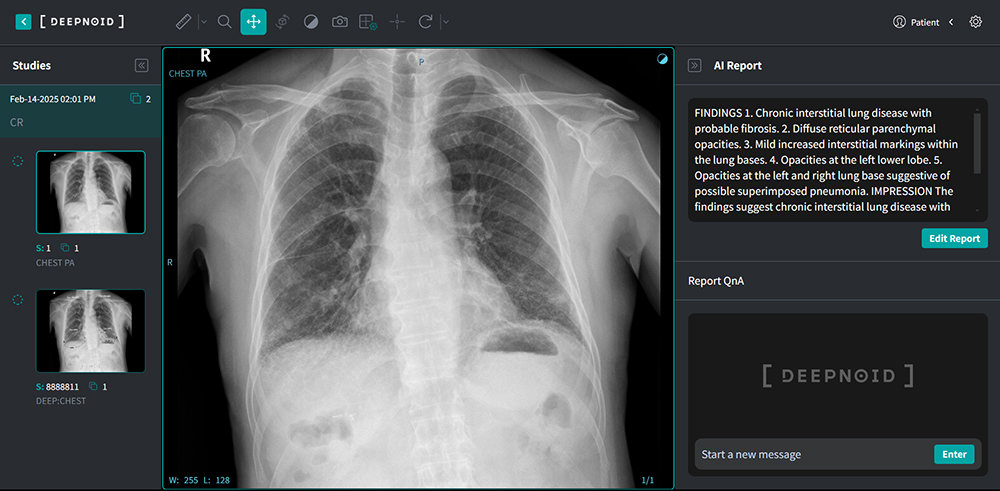

인터뷰에 앞서 김태규 전무에게 딥노이드의 설루션 전반에 대한 소개를 부탁했다. 김태규 전무는 “M4CXR은 흉부 엑스레이 데이터로 판독 소견서 초안을 자동으로 생성하는 설루션이다. 기술 측면에서는 2015년부터 딥러닝 관련 연구를 시작했고, 자기 공명 혈관조영술(MRA) 결과를 기반으로 뇌동맥류를 검출하거나 다양한 병리 영상 등을 통해 대장암, 신장암, 위암 등의 질환도 분석해서 검출하는 기술 등을 개발해 왔다”라고 배경을 설명했다

이를 기반으로 AI 기반 흉부 X-Ray 진단보조 설루션 딥:체스트(DEEP:CHEST)를 개발하고 최근에는 M4CXR로 기능을 업그레이드 중이다. 아울러 AI 기반의 뇌 MRA용 딥 뉴로(DEEP:NEURO), 폐 질환 대응 딥 렁(DEEP:LUNG) 등의 의료 AI 서비스도 개발했다. 이중 딥 뉴로(DEEP:NEURO)는 혁신의료기기로 선정돼 비급여로도 수가가 지급되는 게 특징이다. 산업용 엑스레이를 위한 스카이마루:시큐리티(Skymaru:security), 딥시큐리티(DEEP:Security), 딥팩토리(DEEP:Factory) 등의 설루션도 있다.

국내외 비슷한 기업들이 있는데, 어떤 점에서 차별화될까. 김태규 전무는 “생성형 AI 기술을 통해 판독 소견서 초안을 생성하는 기술이 핵심이다. 이와 관련해 2023년부터 흉부 X레이 생성형 AI 기술 관련한 논문을 쓰고 있고, 올해 안에 이를 기반으로 하는 제품의 인허가를 받을 예정이다. 의료기기 기업으로 생성형 AI를 활용하는 점에서는 독보적이고 차별화된 기술력을 갖췄다”라고 설명했다. 또한 판독 소견서도 폐질환 검출에 최적화됐지만, 흉부 엑스레이도 판단할 수 있는 기관지, 심장, 흉벽, 뼈, 기타 장기까지 복합적으로 결과를 내놓는다는 게 딥노이드의 기술력이라고 덧붙였다.

딥노이드가 진행하는 AI반도체 응용실증지원 사업의 목표는 M4CXR 실증이다. 실증 병원은 서울대병원, 인하대병원, 서울아산병원으로 선정됐고, 각 병원에서 클라우드 기반으로 서비스에 접속해 M4CXR을 사용하며 실증 사례를 만드는 게 목표다. 김태규 전무는 “목표는 세 개 병원이지만 사업기간 내에 더 많은 실증 기관을 확보하려 한다. 1차 의료기관과 국내 공공의료기관, 필리핀 및 베트남, 중동 등 다른 지역에서도 도입할 수 있는 방안을 마련하는 중”이라 답했다.

딥노이드의 NPU 도입은 해외 진출에도 도움이 된다. 현지훈 연구소장은 “사용자는 서비스가 NPU인지, GPU인지 신경 쓰지 않고, 가격과 운영비용만 고려한다. NPU를 활용해 운영 비용이 저렴해진다면 그만큼 더 사용량이 더 늘고 많은 고객을 유치할 수 있다”라면서, “서비스 완성도를 알리기 위해 올해 11월 개최되는 북미영상의학회(RSNA 2025)에 M4CXR을 출품하고, 국산 NPU의 LLM 처리 기능으로 판독 소견서가 생성되는 기능을 알릴 예정”이라고도 덧붙였다.